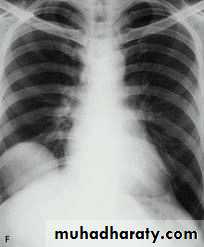

• CXR

• CT scan

• Bronchography

thoracic surgery